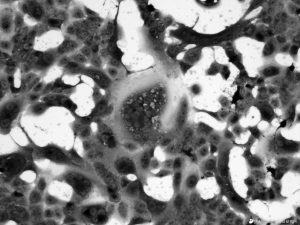

2019nCoV-200130cellculture_niid